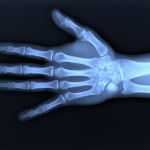

Orthopedic. Orthopedic surgery or orthopedics (also spelled orthopaedic surgery and orthopaedics) is the branch of surgery concerned with conditions involving the musculoskeletal system. Orthopedic surgeons use both surgical and nonsurgical means to treat musculoskeletal trauma, sports injuries, degenerative diseases, infections, tumors, and congenital disorders.